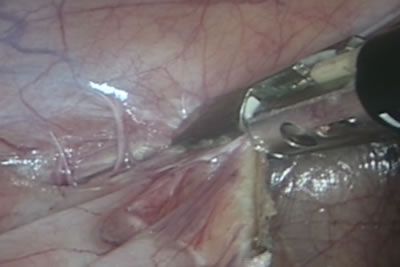

Освобождение желчного пузыря и печени из спаек.

Печень отведена специальным инструментом, который расправляется

в брюшной полости в виде веера.